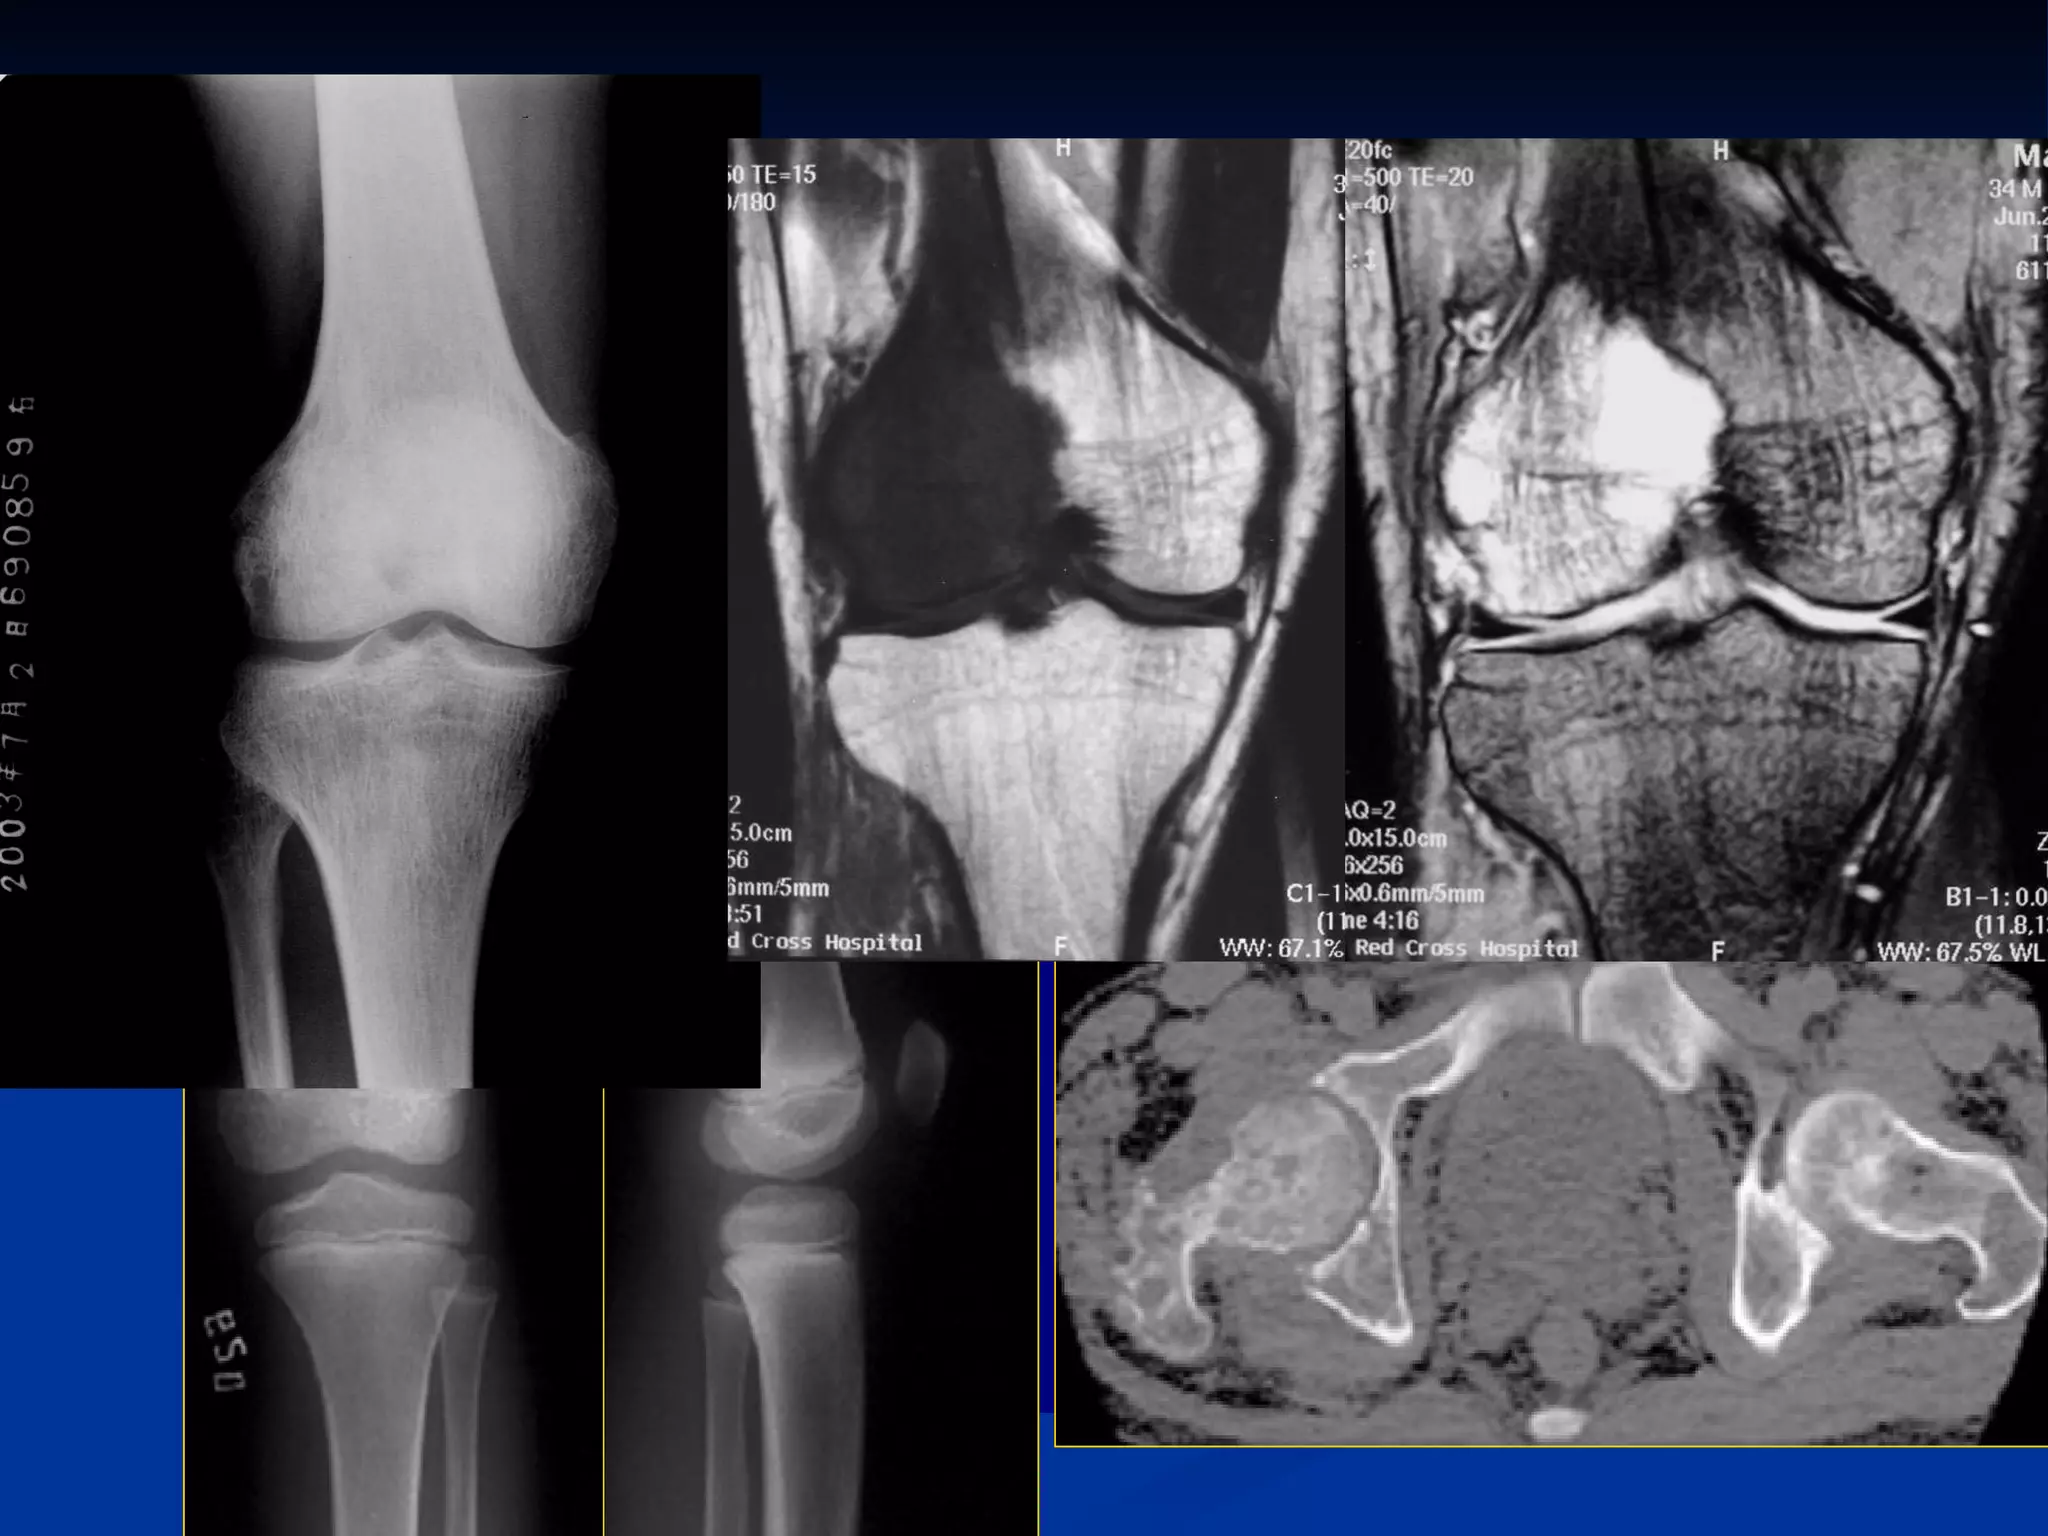

Spine  Normal appearances

Spine Normalappearances